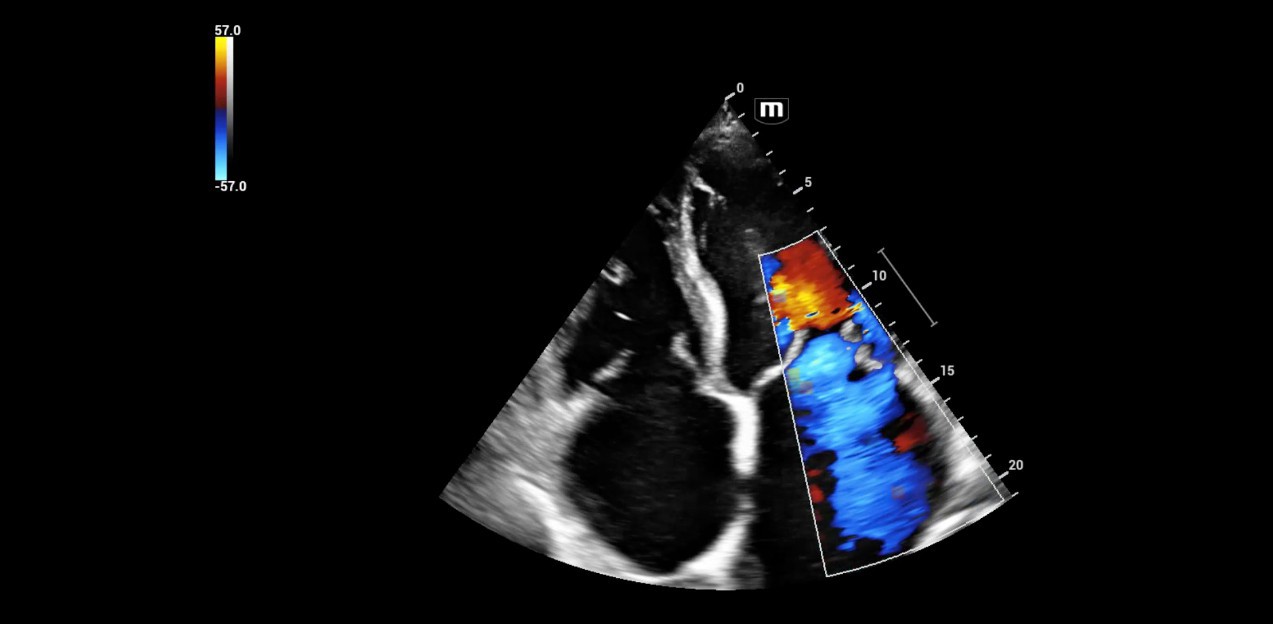

2. Severe mitral insufficiency with tearing of the support apparatus of the posterior valve segment.